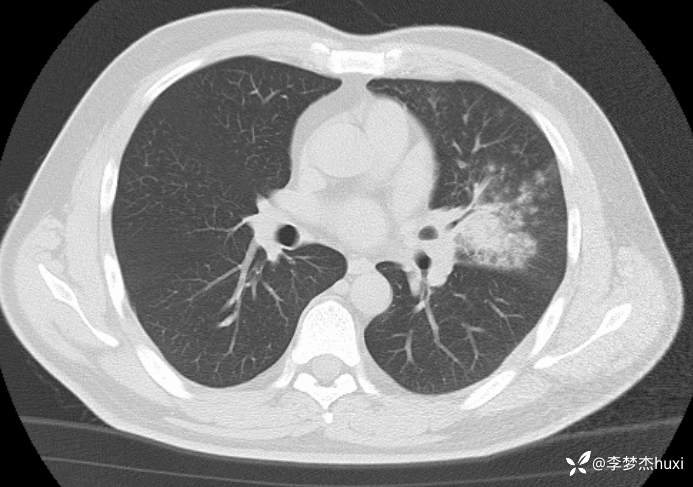

男性40岁,咳嗽、咳痰5天,CT示空洞病变,可能是啥病原菌?

【现病史及既往史】: 1.患者中年 男,患者缘于5天前前无诱因出现咳嗽、咳痰,为黄痰,伴臭味,痰不易咳出,伴发热,最高体温不详,无喘息、憋气,无胸痛,无咯血,无腹痛腹泻,无恶心、呕吐。院外未应用药物治疗,症状无明显好转,为求进一步治疗来院就诊,门诊查胸部CT;双肺炎症,左肺上叶厚壁空洞形成,双肺纹理增重,双侧胸膜局限性增厚,脂肪肝,建议结合临床复查。以“肺炎”收住院;。

【临床诊断】:肺脓肿伴有肺炎。